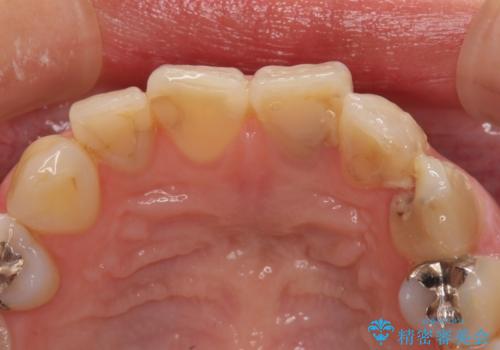

- 長年むし歯を放置してしまっているとのことで来院された患者様です。

神経が除去されている歯、根管治療の必要な歯、むし歯の非常に大きな歯に対してオールセラミッククラウンにて補綴治療を行うこととしました。